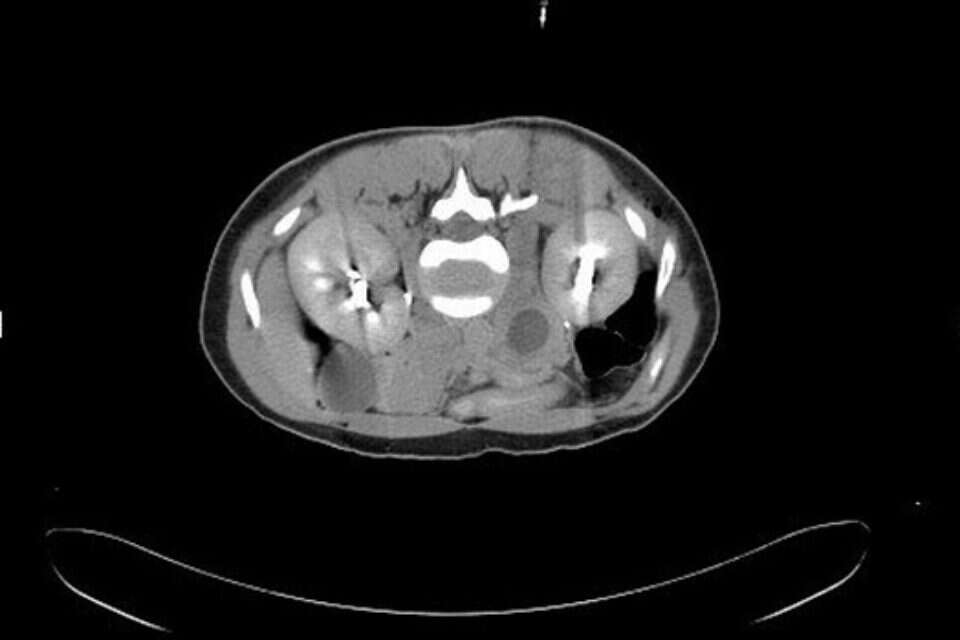

עוברים ברחמה של פעוטה בת 3 שבועות (אילוסטרציה) // עוברים ברחמה של פעוטה בת 3 שבועות (אילוסטרציה)

פעוטה שרק נולדה בהונג קונג אובחנה כמי שנמצאת בהריון עם תאומות. הפעוטה בת השלושה שבועות בלבד, שנולדה להורים מסין, נאלצה לעבור ניתוח וההערכה היא ששני העוברים היו כבר בני שמונה עד עשרה שבועות. בצילום אולטרסאונד הבחינו הרופאים ברגליים, ידיים, עמוד שדרה, צלעות ואפילו מעיים. השניים היו עטופים בעור, אחד מהם שקל 14.2 גרם ואילו השני שקל קצת פחות  - 9.3 גרם. שניהם היו גם מחוברים בחבל הטבור.